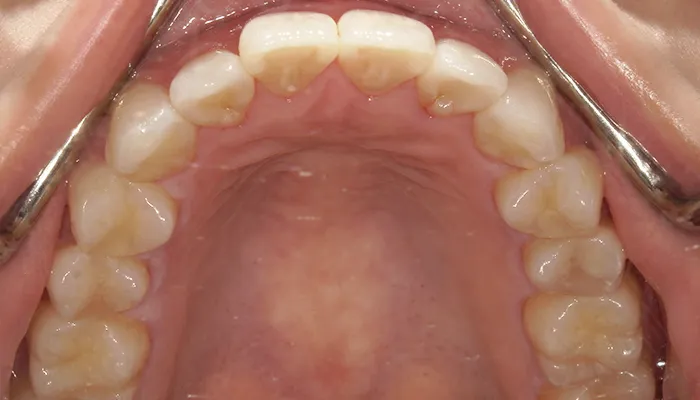

初診時の口腔内写真

術前の口腔内写真

右下5番は大きく崩壊しており、保存不可能な状態でした。

また、下顎前歯部を中心に叢生があり、歯列が不均一でした。咬合関係が不安定で、清掃性も低下していました。

全体的に歯の色もやや黄みを帯びており、患者様からも審美的な改善希望が強くありました。